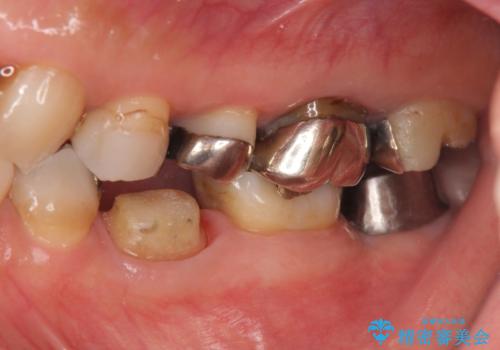

- 左下奥歯の咬合時疼痛を訴えて来院されました。

最後方臼歯周囲には大きな透過像が見られ、破折が強く疑われること抜歯が想定されることを理解していただき銀歯を除去したところ破折が認められたため抜歯を行いました。

今後の機能回復方法としてインプラント治療を希望されたため、将来的に大規模な骨造成が必要とならないよう歯槽堤保存術を抜歯と同時に行いました。

- 50万円(ストローマンインプラント・骨造成・チタンカスタムアバットメント・メタルボンド)費用は治療当時の料金となります